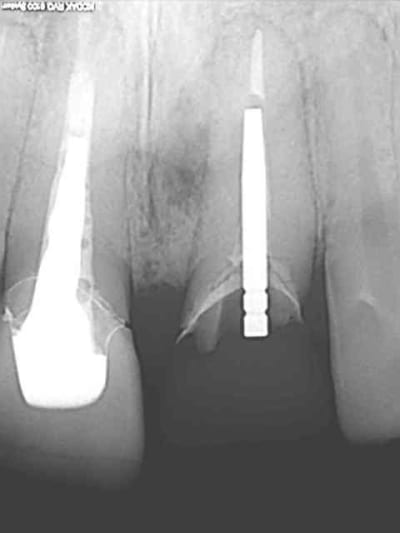

voici encore un autre cas avec du PX encore tout chaud de ce matin...

homme 35 ans veut faire recoller sa couronne 21.

le tenon est tordu, je refais une provisoire mais à la radio je lui dis que j'ai un doute quant à la survie de la dent parce qu'il y a une image pas très nette en mesial de la racine.

je l'envoi faire quelques coupes tomo (vivement que j'ai cone beam! )

le resultat est édifiant et sans appel; la racine est à extraire!

donc je m'y mets ce matin...

1 radio départ

2

OUPS !!

1 radio départ

2-3-4 cas initiale avec provisoire

5 extraction avec periotome

6-7 l'objet du délit...

8 forage

9 jauge de profondeur

10 l'AXIOM PX

(diamètre 4; dans le cas précédent c'était un diamètre 3.4 on voit qu'ici il y a une réduction du diamètre du col de l'implant contrairement au 3.4 pour eviter de fragiliser l'implant)

1 implantation

je n'étais pas du tout sure de le mettre car je n'avais qu'à peine 3à4 mm d'ancrage en apical.

je me suis fais un peu violence pour essayer tout de même quitte à perdre l'implant.

j'ai surtout été très surpris par l'excellente stabilité primaire malgré le peu d'os.

2 -3-4 implant et pilier en place

5-6-7-8-9-10 périotome-extraction-jauge- deuxième jauge-vérification de la profondeur par rapport aux collet des dents voisines-

09/01/2012 à 17h49

séquence prothèse:

1-2-3 élaboration de la provisoire sur le pilier définitif et vérification des contacts occlusaux

4-5- pilier titane angulé à 7° et comblement du hiatus avec du Bioos-collagene qui supporte beaucoup mieux l'exposition que le Bioos simple

6-7-8 ayéh! j'ai fini pour aujourd'hui.

9 radio post op

voili-voilà :

avant d'envoyer le patient passer son cone-beam je n'étais pas convaincu que il y avait un kyste. comme quoi!